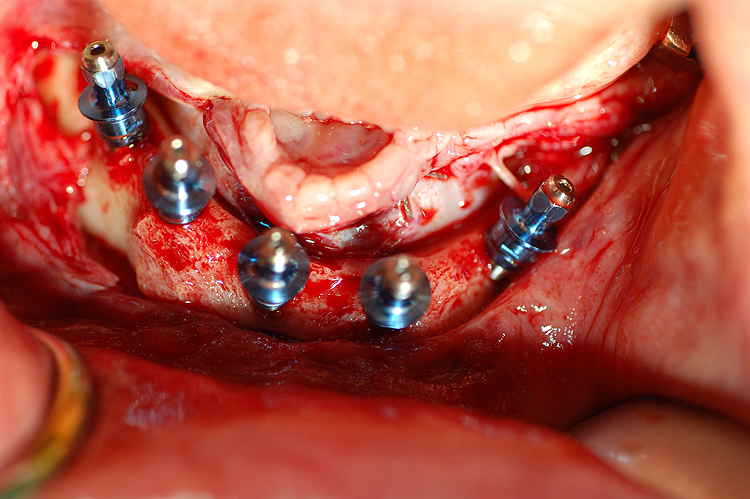

3- Intervento chirurgico.

Eseguita in anestesia locale,

l'operazione risulta semplice e sicura se si rispettano

delle regole. Il dentista deve essere qualificato e deve

aver seguito dei corsi specifici. Per evitare infezioni che

potrebbero causare un insuccesso è importante la sterilità

di tutti questi elementi: strumenti e campo operatorio

dove questi vengono appoggiati, abbigliamento del

dentista e dell'assistente, teli di copertura del paziente.

La cute del viso e l'interno della bocca devono essere

disinfettati. La qualità dell'impianto è anche

fondamentale: la sua sterilità, la forma, le microscopiche

caratteristiche della sua superficie garantiscono

l'integrazione con il tessuto osseo. Bisogna assicurarsi

che l'impianto sia certificato e garantito dalla casa

produttrice. Alcune ditte, sicure dell'eccellenza del

proprio prodotto, includono nel prezzo dell'impianto

anche l'assicurazione!